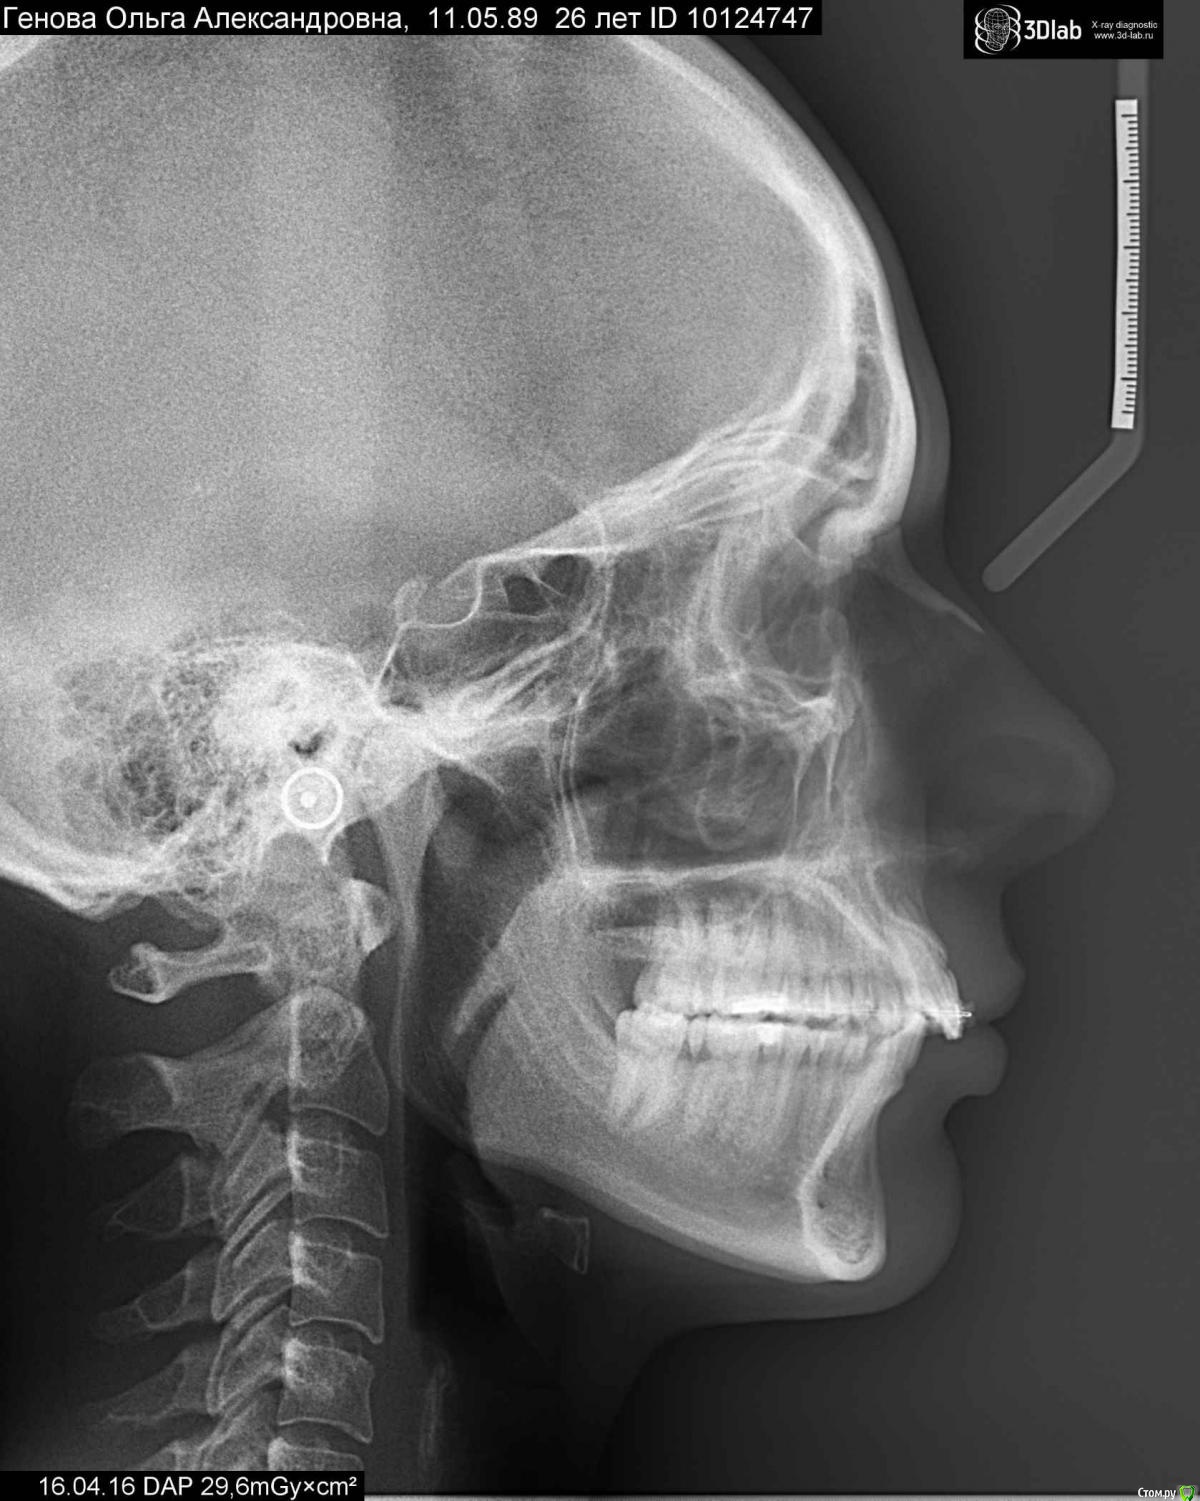

aleksandrovna_o Опубликовано 18 апреля, 2016 Поделиться Опубликовано 18 апреля, 2016 Уважаемые ортодонты, я понимаю, что огромное количество людей с "зубными" проблемами гораздо большими, чем у меня, но прошу просмотреть эту тему. Обратилась к ортодонту, желая выровнять верхние резцы на ВЧ, все 4 ортодонта, к кому обращалась, НЕ направляли на трг, говорили, что у меня заднее положение НЧ и нужно удалить четвёрки (фото в этой теме:http://forum.stom.ru/topic/31021-mozhno-li-obojtis-bez-udaleniia-chetvyortykh-premo/). Удалось уговорить одного из ортодонтов обойтись без удаления, план лечения был след.: выровнять ВЧ и двигать НЧ тягами (резинками), чтобы исправить прикус. Установив брекеты на ВЧ, мой ортодонт ушла в декрет, не предупредив заранее. После последнего визита (2 - я замена дуги) прошло уже почти 3 месяца, доктор недоступен, в клинике тоже не знают, когда она вернётся. Решила забрать свой слепок, пошла к ортодонту, который заменял моего врача. Осмотрев меня, этот доктор ошарашил неожиданной информацией:- тяги у людей в возрасте больше 24 лет (мне 26) не помогут, задняя челюсть опять уйдёт назад после окончания лечения;- нужны миниимпланты, которые будут тянуть зубы на ВЧ назад. Хоть я ничего не понимаю в медицине, но у меня закрались сомнения: если у меня заднее положение НЧ, то зачем же задвигать зубы с помощью имплантов на ВЧ и получается блокировать НЧ, усугубляя ситуацию?Решила сходить к ещё одному ортодонту, он посмотрел ТРГ и сказал что:- в 60% случаев, если создать правильные контакты между зубами, то НЧ сама встанет в правильное положение (тут сразу я подумала об оставшихся 40%);- также нужно использовать тяги, чтобы двигать НЧ;- НЧ часто сдвигается назад из-за того, что мы сутулимся, нужно не забывать держать спину ровно. Столько разных мнений! Подскажите, пожалуйста, действительно ли у взрослого человека бесполезно выдвигать резинками НЧ, если да, то что же мне делать?Буду очень признательна. Ссылка на комментарий